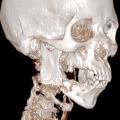

Tumeur à cellules géantes

TUMEUR A CELLULES GEANTES